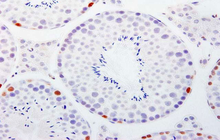

- Perform tunnel technique to evaluate apoptosis

Histological methods includes sample processing in the pathology laboratory, preparation of the slide and its examination under a microscope, sample fixation, molding, microtome cutting, staining and assembly of the slides.